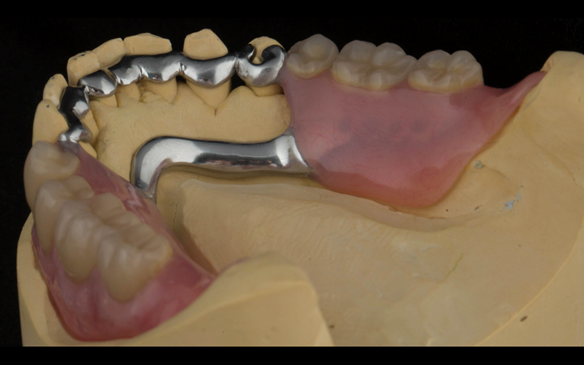

This newsletter describes in step by step detail the transition from acrylic based immediate dentures to metal based definitive dentures.

- Definitive dentures (Mk 2) – complete upper metal reinforced and lower cobalt chromium based partial of hygienic Scandinavian design to be made 9 - 12 months after extractions of all upper teeth and LR5 and LL4